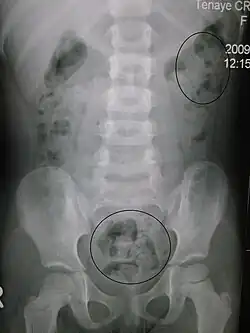

Constipation in a young child seen on X-ray. Circles represent areas of fecal matter (stool is white surrounded by black bowel gas). | |

Abdominal X-rays are generally only performed if bowel obstruction is suspected, may reveal extensive impacted fecal matter in the colon, and may confirm or rule out other causes of similar symptoms.[26][17]